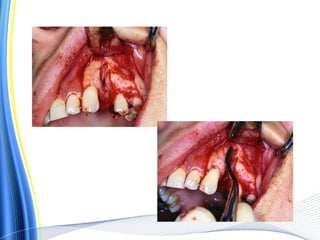

a, b. Surgical extraction of a mandibular

molar

with hypercementosis at the distal root tip.

The envelope

flap is reflected, part of the buccal plate is

removed, and the

tooth is sectioned buccolingually at the crown

as far as the

intraradicular bone

Extraction of the mesial portion of the tooth,

which includes the crown and root

Widening of the alveolus with a round bur, so

that removal of the root is possible without

fracturing the bulbous root tip